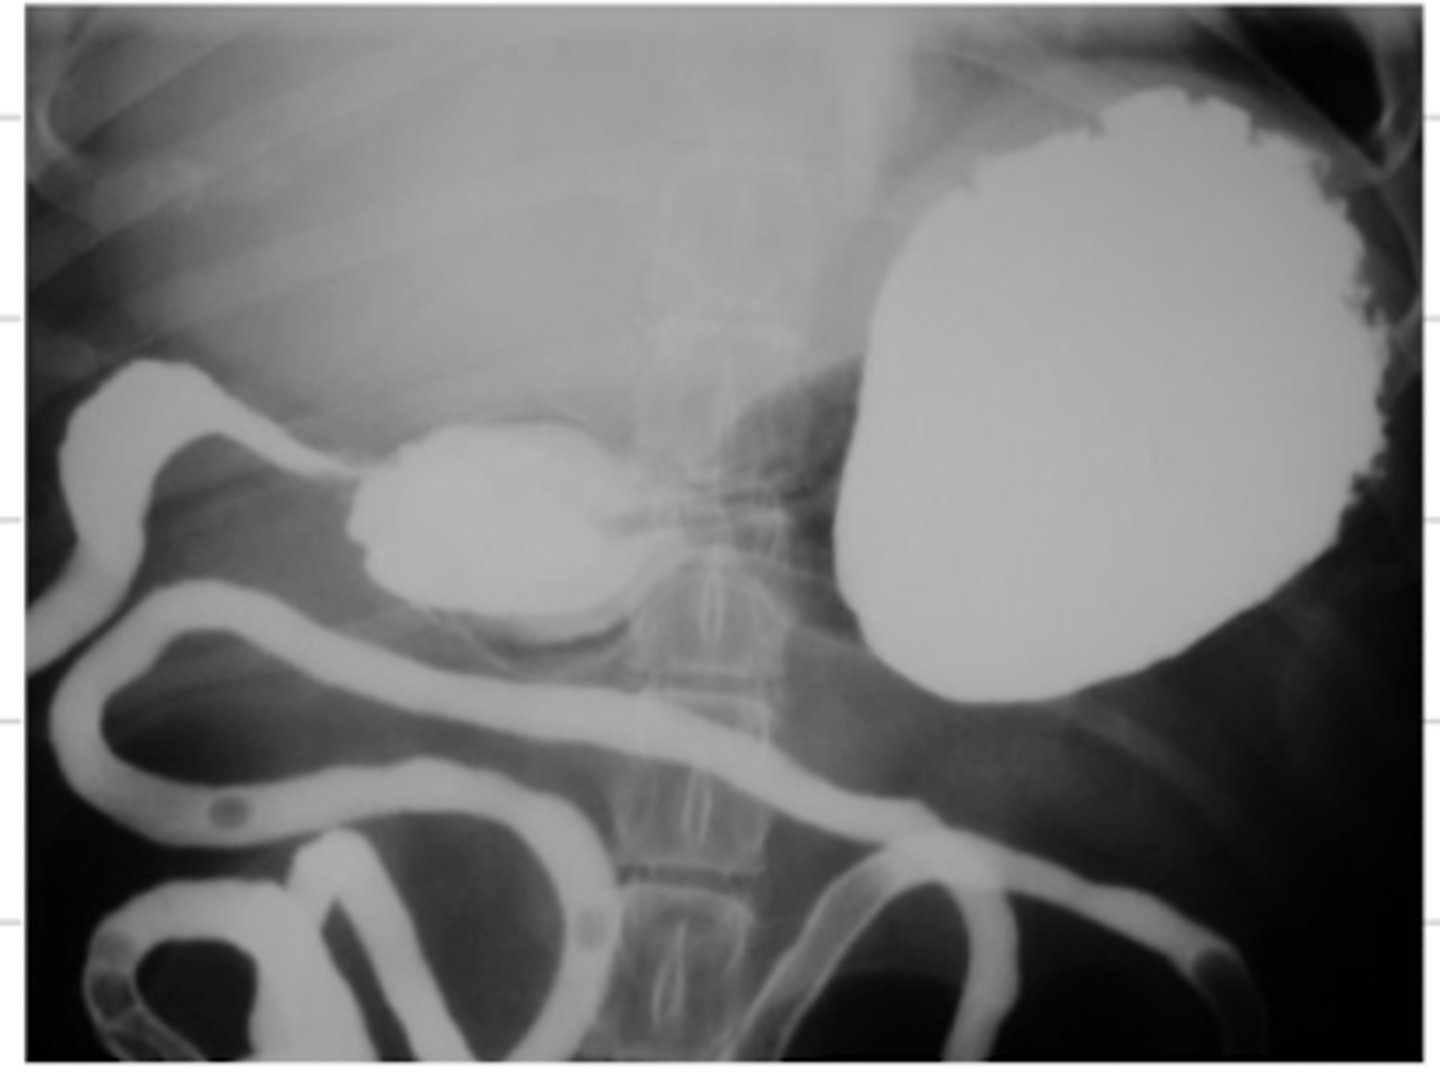

excretory urogram

what contrast method is used in this radiograph?

a type of contrast radiograph used to visualize the urinary system- where we put contrast in the patient's IV, so that it goes with the blood to the kidneys and out through the ureters to the rest of the urinary tract

what is an excretory urogram?

retrograde urogram

what contrast method is used in this radiograph?

a type of contrast radiograph used to visualize the lower urinary system- we put contrast in the urinary catheter so it goes directly to the bladder and urethra

what is a retrograde urogram?